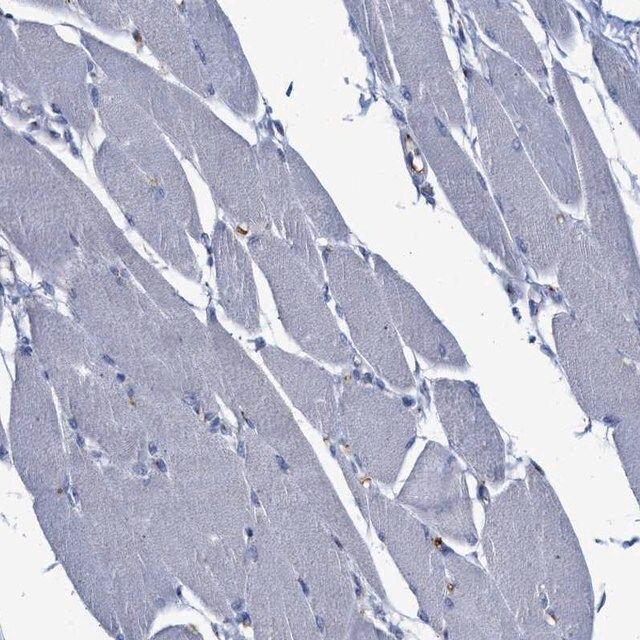

在兔中生产的抗-CCL2,一种Prestige抗体,是由Human Protein Atlas(HPA)项目(www.proteinatlas.org)开发和验证。每一种抗体都已通过免疫组织化学对数百个正常组织和疾病组织进行了检测 。通过单击图像库链接,可以在Human Protein Atlas(HPA)站点上查看这些图像。该抗体也在免疫荧光和蛋白印迹中进行了测试。 欲查看这些 实验方案 以及有关Prestige抗体和HPA的其他有用信息,请访问 sigma.com/prestige。

- 44例正常人类组织以及20例最常见癌症类型组织的IHC组织阵列。